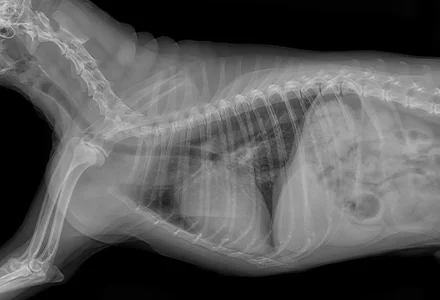

• 흉부 방사선 검사

폐수종 여부, 심장의 전체적인 크기와 모양, 주변 혈관 상태 등을 확인하여 심장 질환으로 인한 이차적인 변화를 평가하고

다른 호흡기 질환과의 감별에 도움을 줍니다.

(흉부 X-ray 판독. 심장초음파 전문 지원)